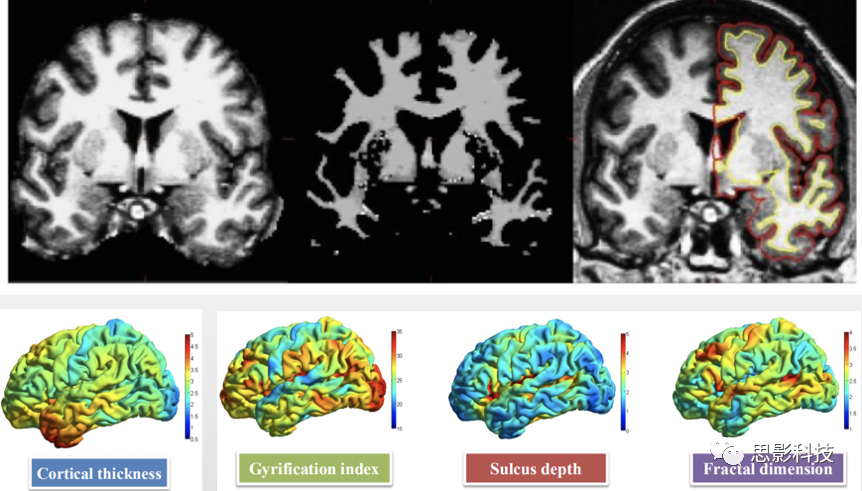

三、基于表面的形態(tài)學測量分析(SBM

基于表面的皮層指標計算,也可以精確地實現(xiàn)。

1.組織分割與皮層重建。對結構像進行分割,并重建皮層。

2.皮層指標計算。主要有:

1) 常規(guī)皮層指標,包括皮層厚度、曲率等;

2)復雜度指標,包括局部回指數(shù)、腦溝深度、分形維度等指標。

圖示.組織分割、皮層重建、皮層指標。

3.統(tǒng)計分析(頂點水平)。可基于實驗設計進行參數(shù)檢驗(包括T檢驗與方差分析,參考VBM統(tǒng)計)??稍谶m當場景進行多重比較校正,包括Monte Carlo Simulation等。

4.基于ROI的統(tǒng)計分析。基于表面分割腦圖譜(如DK Atlas)提取指標值,在ROI水平進行參數(shù)檢驗;根據(jù)統(tǒng)計分析(頂點水平)的結果確定感興趣區(qū)域,提取感興趣區(qū)域的指標,與臨床行為量表進行相關性分析。

5.結果可視化。根據(jù)結果形式,可繪制渲染視圖、散點圖等。注:數(shù)據(jù)處理過程中,會檢查圖像分割、皮層重建狀況;如有必要,會進行手工修正。